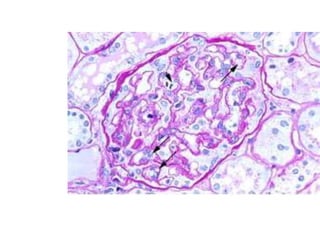

 Glomerular endotheliosis (unique)

 Endothelial cells are swollen ; glomerular capillaries

appear bloodless

 Glomerulus may also herniate into proximal tubules

 Endothelial cells maybe vacuolated with lipid

 Silver staining : string of beads appearance

 Kidney  Glomerularendotheliosis (unique)  Endothelial cells are swollen ; glomerular capillaries appear bloodless  Glomerulus may also herniate into proximal tubules  Endothelial cells maybe vacuolated with lipid  Silver staining : string of beads appearance